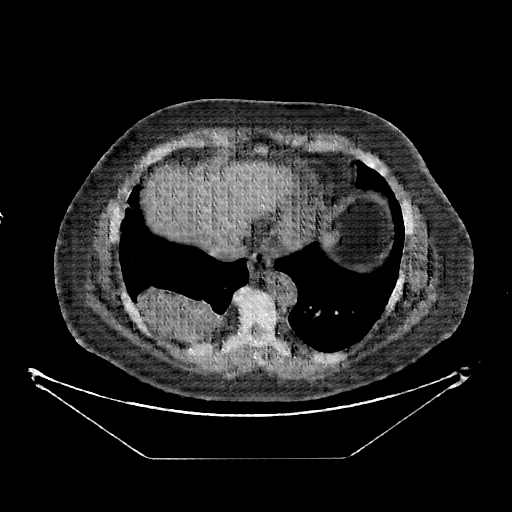

Generated VENOUS CT scan (A→B translation)

No window - Raw intensity values

Lung window (WL -600, WW 1500 β†’ Low βˆ’1350, High +150)

Mediastinum window (WL 40, WW 400 β†’ Low βˆ’160, High +240)